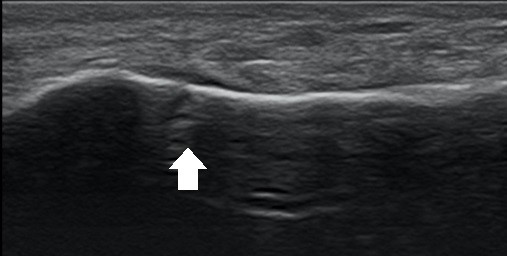

不管是「骨裂」或「線性骨折」都不是正式的醫學名詞,只是被大家用來描述一群X光上比較不明顯的骨折,會大量出現這樣的使用可能是跟肌肉骨骼超音波的進步與普及有關。超音波的檢查對骨頭表面的變化敏感度非常高,X光影像上難以辨識、甚至根本不可能看得到的裂痕,在超音波下往往是無所遁形(圖一)。許多以往必須靠昂貴的電腦斷層甚至磁振造影檢查才能確診的骨折,有了超音波的幫忙可以更快地做出正確的診斷。常見會被診斷為「骨裂」或「線性骨折」損傷包括:

圖(A) 65歲女士右足內翻受傷,X光影像僅勉強在第五蹠骨疼痛處看到有疑似裂痕,無法確認。(B) 超音波影像診斷骨折的依據包括:骨頭表面不連續,局部骨膜下血腫,輕壓即有明顯疼痛。